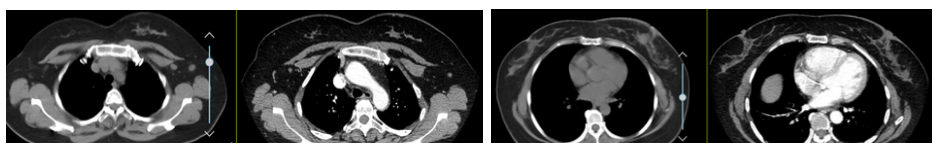

考虑患者在曲妥珠单抗治疗过程中病情进展,故予以二线抗HER-2治疗。 于2018年11月15日开始行第一周期“LN”方案治疗:长春瑞滨 100 mg po d1/d8+拉帕替尼 1250 mg po qd,q3w。治疗后主要发生不良反应:恶心、呕吐及腹泻,CTCAE Ⅱ级;粒细胞减少伴发热,CTCAE Ⅳ级,均经对症治疗后有好转。2018年12月6日行第2周期“LN”方案减量治疗:长春瑞滨 90 mg po d1/d8+拉帕替尼 1250 mg po qd,q3w,并预防性予以重组人粒细胞集落刺激因子等支持治疗后,无明显不良反应发生。2周期后复查CT,2018年12月20日胸部CT增强(图6)示:两肺淡薄小结节,较前(2018年5月22日)部分结节不明显,余相仿;左肺舌段纤维灶;左乳乳晕后方皮肤增厚,较前肿块影不明显、两腋下淋巴结缩小。2018年12月20日上腹部CT增强(图6)示:肝Ⅷ段结节灶,稍低密度结节,边缘稍模糊,径约15 mm,增强后边缘似见强化;脂肪肝;双肾小结石;胆囊术后。

综上显示乳腺病灶及肝脏转移灶均缩小,疗效:PR。后继续本方案治疗至2019年6月,期间定期复查评估,疗效仍为PR。

图5 2018年12月20日 LN方案后第一次疗效评价 胸部CT增强

图6 2018年12月20日 LN后第一次疗效评价 上腹部CT增强